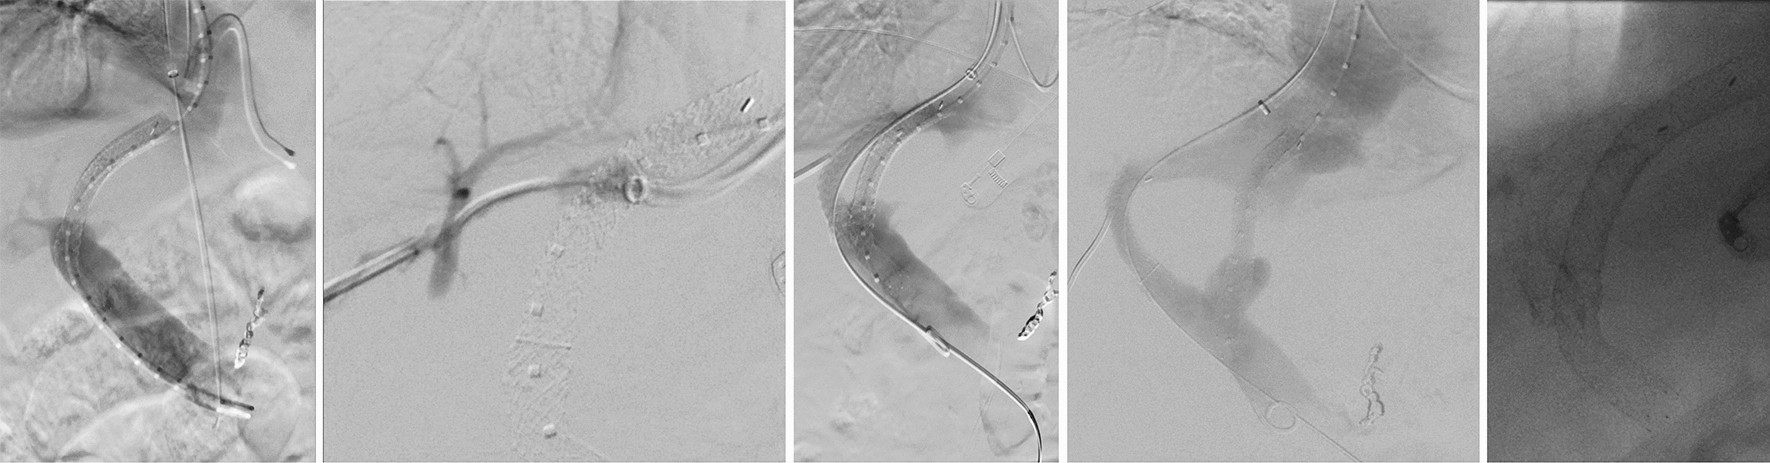

Figure 4

Second TIPS placement. A second TIPS implantation from the right hepatic vein to the right portal vein was necessary in the same patient due to persistent gastrointestinal hemorrhage. The initial TIPS remained patent.